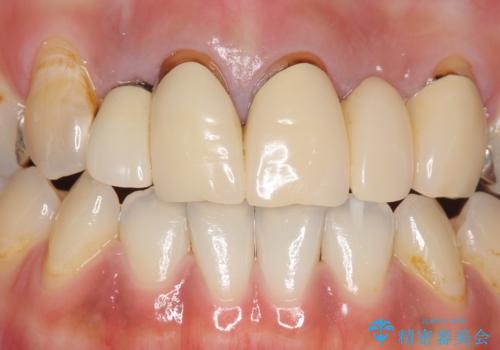

- 昔入れた被せ物と歯茎の間の隙間が気になると来院された方の症例です。

右上1、2番目の歯と左上1、2、3、番目の歯のブリッジを除去し、オールセラミッククラウンによる補綴を行うことで見た目を改善しました。

今回用いたオールセラミッククラウンはジルコニアフレームという白い素材の上にセラミックを盛っているため、審美性が非常に高いのが特徴です。

また、ジルコニアは人工ダイヤモンドの材料にも使われているほど高い強度を持っており、そのためオールセラミッククラウンは審美性だけでなく、奥歯やブリッジの補綴も可能とするクラウンです。